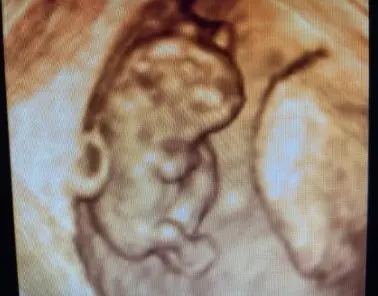

Tercer trimestre

En esta etapa continuamos con el control de la analítica y los tratamientos necesarios, que se realizan en todas las consultas, la identificación de la situación fetal, su crecimiento, la valoración de la placenta y del líquido amniótico. Así como el estudio de la circulación materno-fetal mediante el Doppler color de La arteria umbilical. A través de ecografías y estudios complementarios se comprueba el bienestar del bebé, su evolución final y cualquier cambio que pueda requerir una vigilancia más estrecha. Este control permite llegar al final del embarazo con la máxima seguridad tanto para la madre como para el bebé.

Cara

Doppler de la Arteria Umbilical